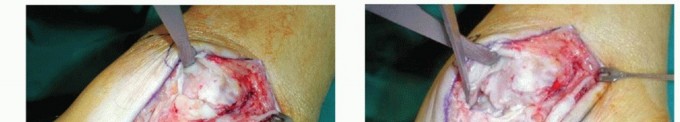

continuity is lost.8 Most ligament tears are located on the proximal insertion; this is best seen by a completely free insertion area of the ligament on the malleoli (TECH FIG 1).

- TECH FIG 1 • Avulsion of the anterior superficial layers from the medial malleolus. Arthroscopy typically reveals a completely free insertion area of the ligament on the medial malleolus.